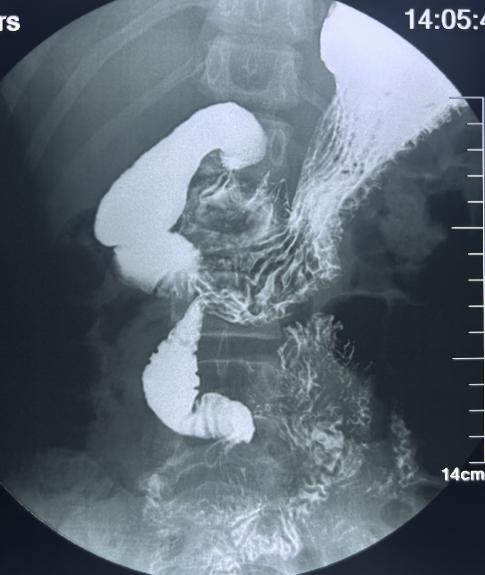

· 上消化道造影:能显示十二指肠位置异常、空肠位于右侧腹部等特征性表现;